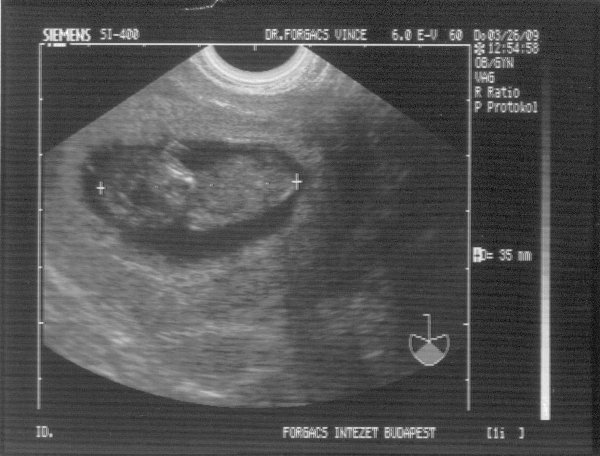

És ezt írta a doki:

"A terhes méh üregében egy szabályos petezsák látható. Átmérője 52 mm. Benne egy élő embryo. CRL: 35 mm. Ritmusos szívműködés, négy végtag és intenzív embryonális mozgás látható. A korábban látott többi petezsák közül már csak egy kicsiny 12 mm-es látszik, benne embryonális elem nem látható. A méh környezetében kóros képlet nincs.

A látott kép AIH révén fogant, élő, intact, 10 hetes singularis intrauterin terhességnek felel meg."